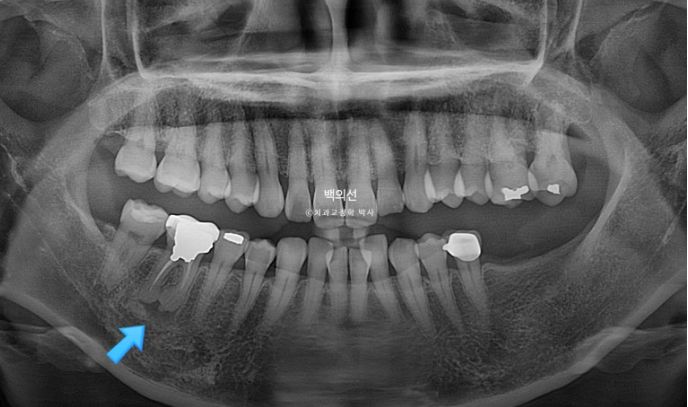

파란화살표 임플란트를 해넣기 위해서는 교정으로 내려온 대합치를 합입 시켜 올려야 합니다.

특히 내려온 큰어금니들 중 맨 뒤 제2대구치는 살릴 수 없어 타병원에서 발치진단이 나온 상태입니다.

잇몸이 뿌리끝까지 내려가 상태가 좋지 않습니다.

다른 문제가 하나 더 있습니다. 파란 화살표 치아는 신경치료 된 치아인데 뿌리끝에 염증이 있습니다.

이 치아 역시 타병원에서 쓸때까지 쓰다가 문제 생기면 발치 후 임플란트 하는 걸로 알고 계셨습니다.

파란화살표 문제의 치근단 염증은 초진에 비해 커지지 않고 잘 유지되었습니다. 치료계획상 이동이 전혀 일어나지 않도록 했기 때문입니다.

치근 평행도는 처음보다 좋아졌으며 치근흡수는 없습니다.